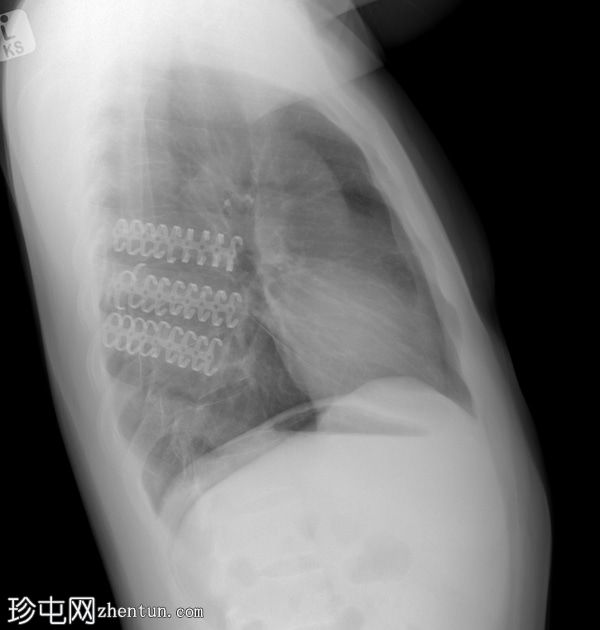

先前在外部医疗机构接受肋骨切开复位内固定 (ORIF) 后进行的 X 光检查。先前曾遭受高速摩托车事故造成的多发性创伤。

正面

左侧锁骨已行 ORIF,远端骨折处采用钢板、螺钉及钢丝环扎固定,伴有持续性皮质台阶状缺损。

3D 肋骨夹正下方固定左侧第 5 至第 7 肋骨。骨性愈合良好,对位良好。

先前创伤和血胸导致左侧膈肌轮廓消失,肋膈角残留。

本病例为高速摩托车事故后,使用3D钛肋骨夹固定先前移位的左肋骨骨折的病例。